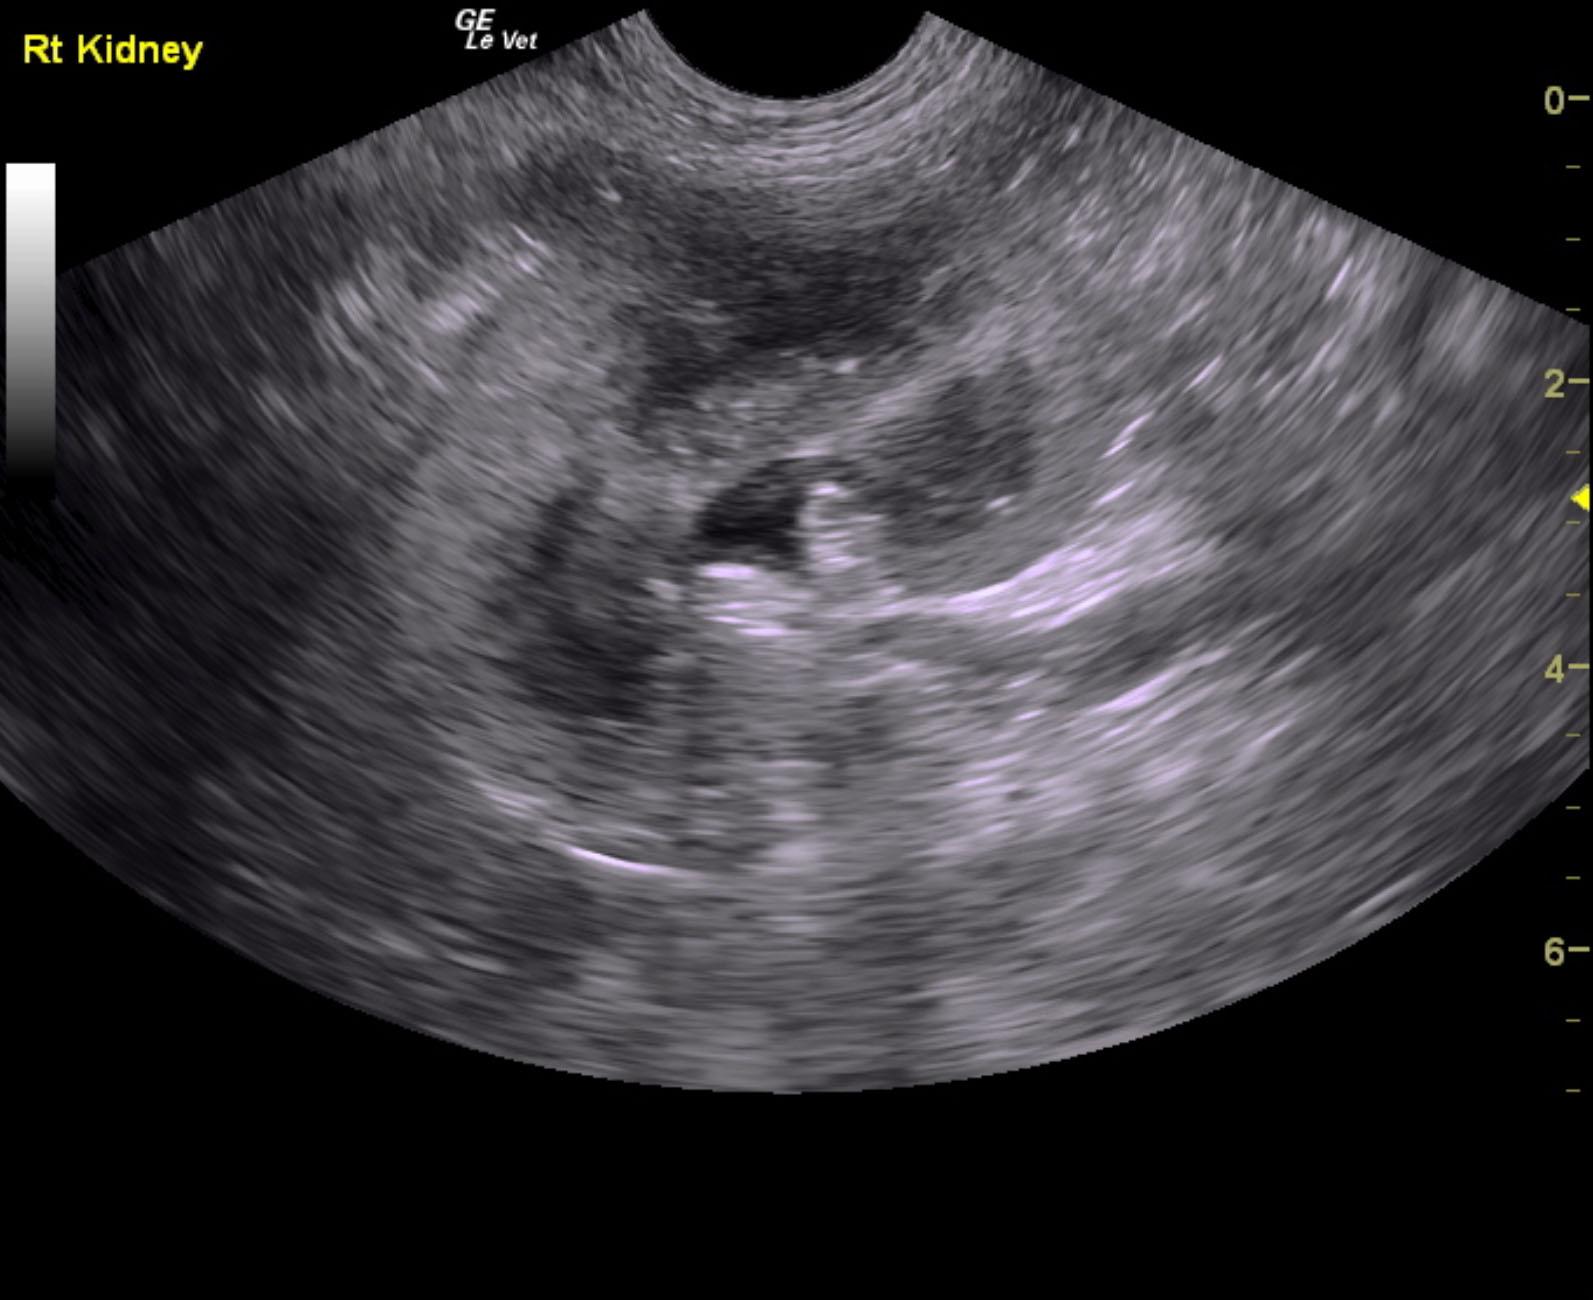

A 5-years-old male neutered Shih Tzu was presented for evaluation of urethral obstruction that had been managed with catheterization. Urinalysis showed SG of 1.008 and proteinuria. Abnormalities on CBC and serum biochemistry were neutrophilia and monocytosis, elevated phosphorus, and azotemia; the latter had improved after being catheterized.